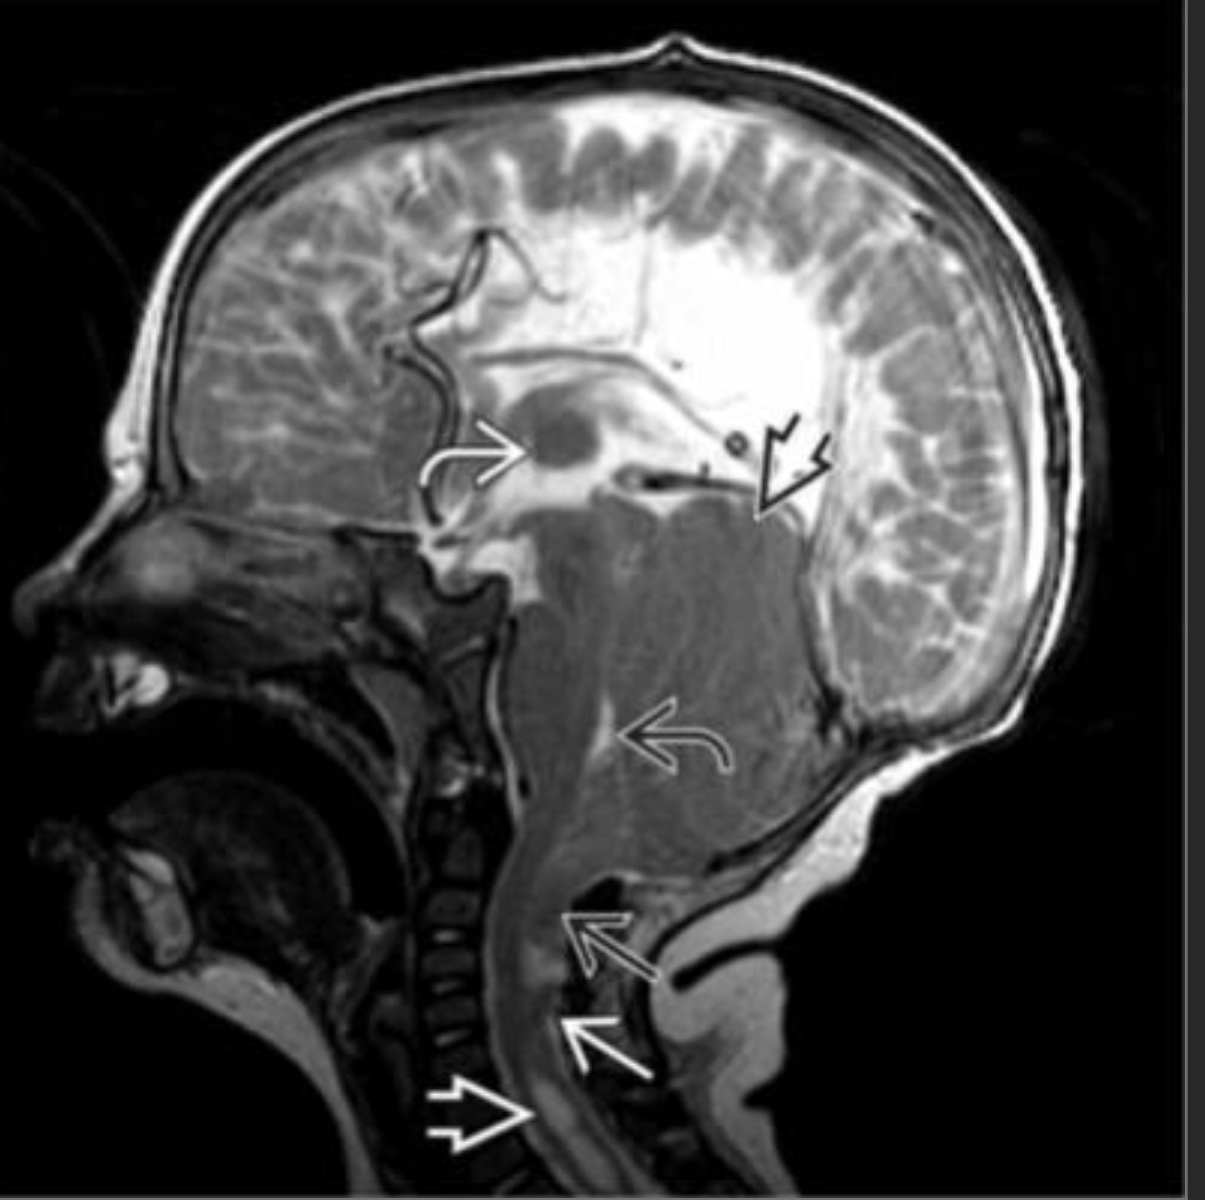

Chiari II malformation

Sagittal T2WI MR shows an inferiorly herniated cerebellar vermis below the foramen magnum, an elongated and flattened 4th ventricle , a low-lying cervicomedullary junction with kinking , an upper cervical spinal cord syrinx , a towering cerebellum , and an enlarged massa intermedia, tectal beaking, stenogyrea (elongated and flattened gyri), dysgenesis fo the corpus callosum

result of myelomeningocele w/CSF loss and ‘sump’ type effect on posterior fossa

Chiari I Malformation

isolated low lying cerebellar tonsils

usu don’t need surgery

occasionally has a syrinx